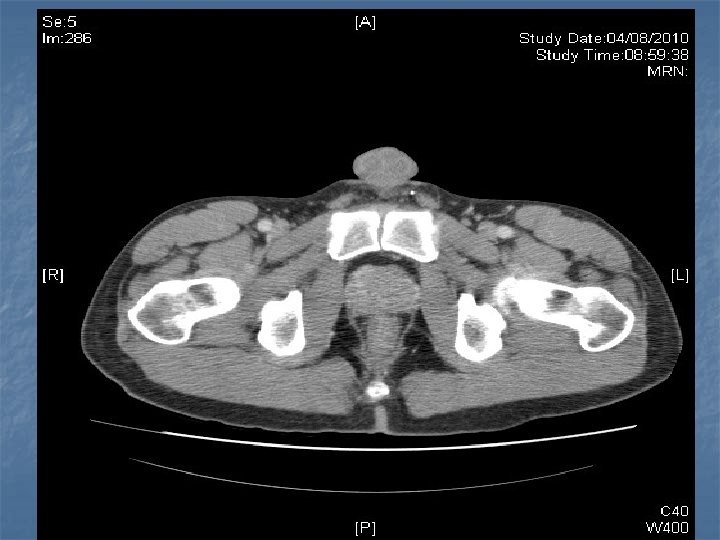

n n n PRETREATMENT INVESTIGATIONS: FBC, Renal and liver function, LDH, urate, Ig. GS. Histology review. Marrow aspirate+trephine (cytogenetics, immunology) CD 4 , HIV viral load. CT Scans. (MR Brain) (PET scan ) Echo / LVEF CMV, Hep B+C, Toxoplasma serology MAI screen. LP for CSF cytology +/- intrathecal Rx. (DLBC , Burkitt, Plasmablastic).

n n n PRIMARY CNS LYMPHOMA Typically occurs with marked immunosuppression CD 4<50. Marked reduction in incidence post HAART. Always EBV positive DLBC NHL. Commonly multifocal brain lesions. n High dose methotrexate iv Followed by brain XRT. n Poor prognosis survival months to 1 -2 years. n